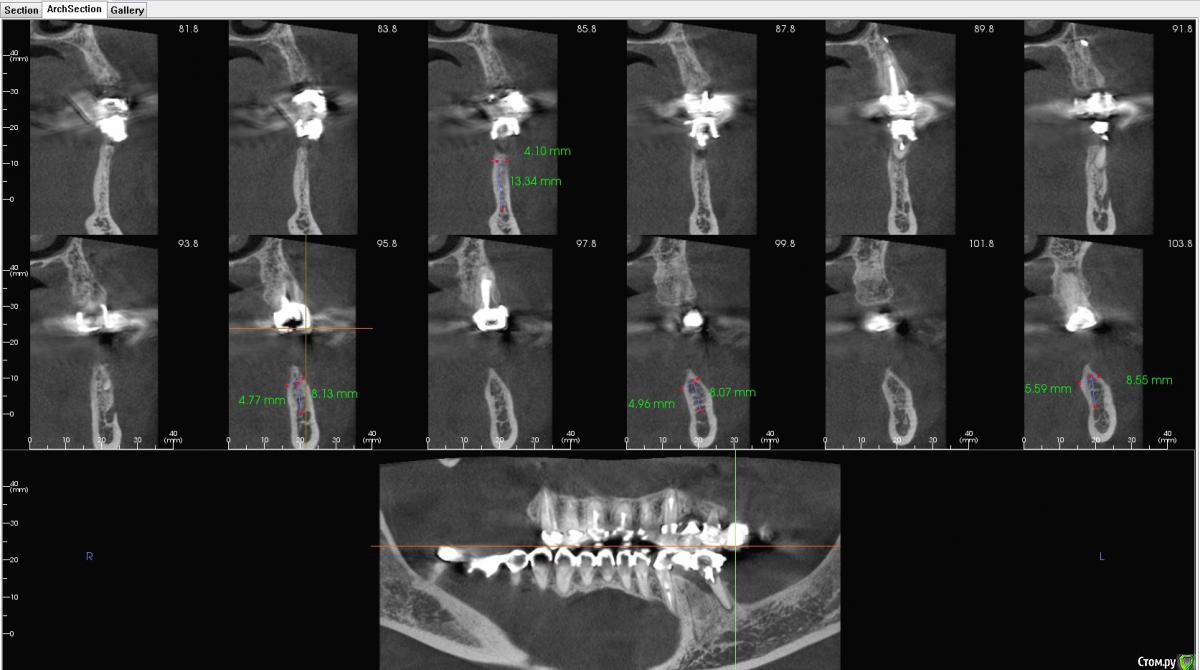

kamranchick Опубликовано 31 октября, 2018 Автор Поделиться Опубликовано 31 октября, 2018 Шаг 2 мм... Ссылка на комментарий

Bier Опубликовано 2 ноября, 2018 Поделиться Опубликовано 2 ноября, 2018 я честно говоря не понял в каком месте среза сколько кости. Где-то кости достаточно для установки имплантата без пластики, где-то нет. Ссылка на комментарий

kamranchick Опубликовано 3 ноября, 2018 Автор Поделиться Опубликовано 3 ноября, 2018 вот еще такие реформаты Ссылка на комментарий

Bier Опубликовано 3 ноября, 2018 Поделиться Опубликовано 3 ноября, 2018 блин, Камранчик, я вообще не понимаю в какую зону ты хочешь ставить и как твою нарезку прикрепить к панораме, которая ниже. Никакой системы координат нет.Короче там, где гребень 4.7 - можно крутить и не делать пластик. Ссылка на комментарий

Тимур86 Опубликовано 3 ноября, 2018 Поделиться Опубликовано 3 ноября, 2018 поставь 5-6-7 и консоль на 4 Ссылка на комментарий